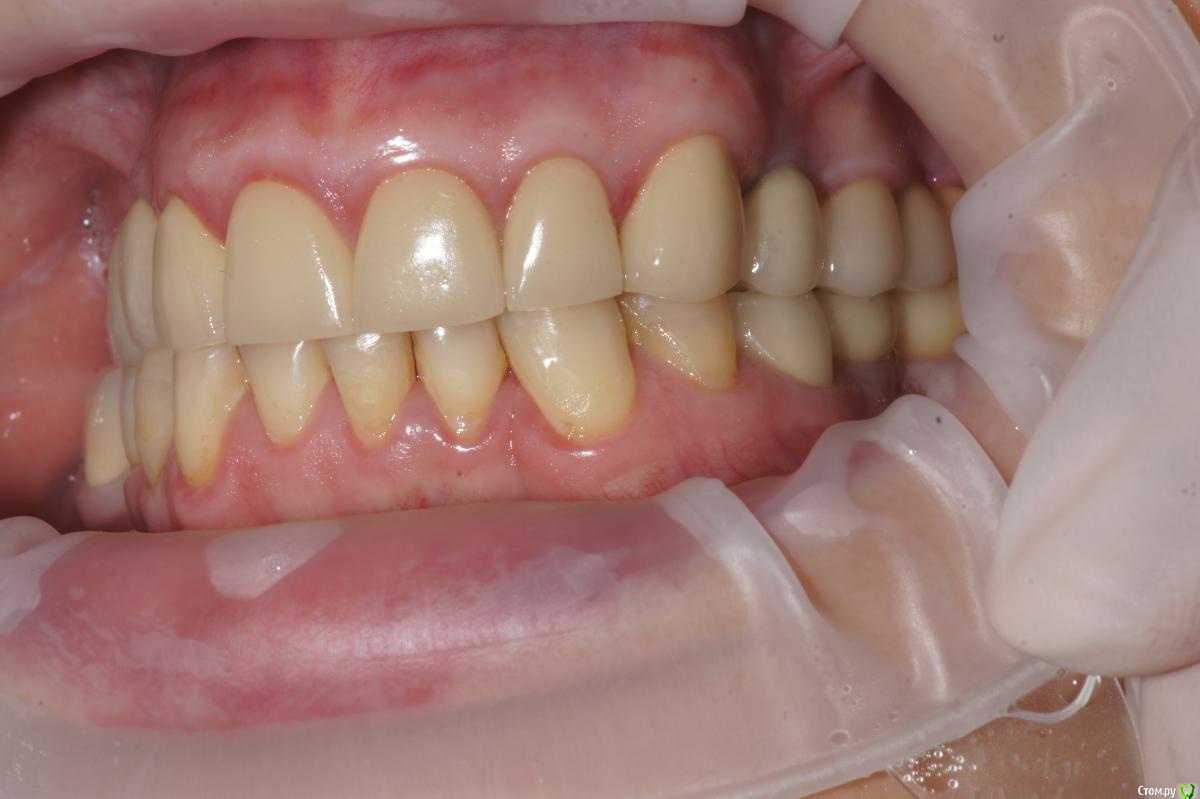

Alexandr_doc Опубликовано 21 сентября, 2018 Поделиться Опубликовано 21 сентября, 2018 Доброго всем времени! Пациентку протезировал доктор, которого уволили по ряду причин, обратилась ко мне на этапе после протезирования с жалобами на болезненность в области фронтальной группы зубов 1.2, 1.1, 2.1, 2.2, 2.3 при дотрагивании языком или пальцем. Перкуссия положительная как в вертикальном так и горизонтальном направлении. Установлены одиночные керамические коронки на каркасе из диоксида циркона. Отек, покраснение в области переходной складки отсутствует, также отсутствует болезненность при пальпации. Подвижность 1 степени. Прилагаю фотографии на этапе обращения. Ранее, на этапе протезирования было принято решение о депульпировании фронтальной группы тк присутствовала пульпитная симптоматика, после чего состояние улучшилось и остается стабильным по сей день. Предположил несколько причин оставшейся симптоматики: 1) несостоятельно проведенное эндо лечение - вариант отмел тк по прицельным снимкам и кт отсутсвуют очаги воспалительных процессов 2) некорректно изготовленные искуственные коронки ( глубокая поддесневая препаровка и агрессивный контур коронки ) 3) - окклюзионная перегрузка. Совместно с пацинеткой принято решение о снятии коронок во фронтальном отделе, была предупреждена о том, что возможно не получить хорошей динамики. С переменным успехом картина после нескольких корректировок временных коронок остается преждней. Болезненность на прежднем уровне, плюс по ходу наблюдения пришлось снять мост с опорой на уровне имплантатов, тк имели место быть воспалительные процессы в проекции имплантата 1.5. С удовольствием отвечу на все вопросы и приму любую критику. Ссылка на комментарий

Дмитрий Л. Опубликовано 21 сентября, 2018 Поделиться Опубликовано 21 сентября, 2018 Маргинальной гингивит. Нависающие края? Мягкий налет под коронками? Остатки цемента? Скоро будет пародонтит. Ссылка на комментарий

Alexandr_doc Опубликовано 21 сентября, 2018 Автор Поделиться Опубликовано 21 сентября, 2018 Маргинальной гингивит. Нависающие края? Мягкий налет под коронками? Остатки цемента? Скоро будет пародонтит.Специально приложил прицельные снимки с временными коронками, где нависающие края? Цемента, лежащего тоннами там нет, думаю, что с корявыми временными коронками выкладывать пост не стал бы Ссылка на комментарий

Alexandr_doc Опубликовано 21 сентября, 2018 Автор Поделиться Опубликовано 21 сентября, 2018 Точно ли на кт нет изменений на корнях зубов? Мне на рентгеновских снимках что-то видится. жесткая каппа на верхний зубной ряд - я бы начал с этого.Нижние резцы устойчивы?Чем вам не нравится глубокая поддесневая препаровка? Десна выглядит также как и на интактных зубах НЧ.Как проверяется работа на предмет локальной перегрузки - не знаю, расскажите пожалуйста.На кт изменений нет, мне хотелось их найти, но нет. Мне будет не сложно сделать срезы и приложить их к посту, рассматривал некачественное эндо как один из первых причинных факторов. Жесткая капа какая? Какой дизайн и схему порекомендуете? Десна действительно сейчас выглядит также как и в других участках. При гипсовке в ЦС проверены: наличие первого контакта на фронтальной группе, проверена схема направляющих, распределение контактов на моделях. Ссылка на комментарий